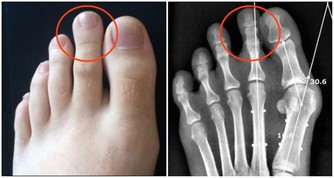

賴床會導致尿液在體內長時間的滯留,於是尿液當中的有毒物質就會損害我們身體的健康。另外,長時間的賴床,會減緩人體的血液循環,導致營養在體內不能很好的傳送,於是肌肉和關節中代謝產生的物質也不能被排除體外。